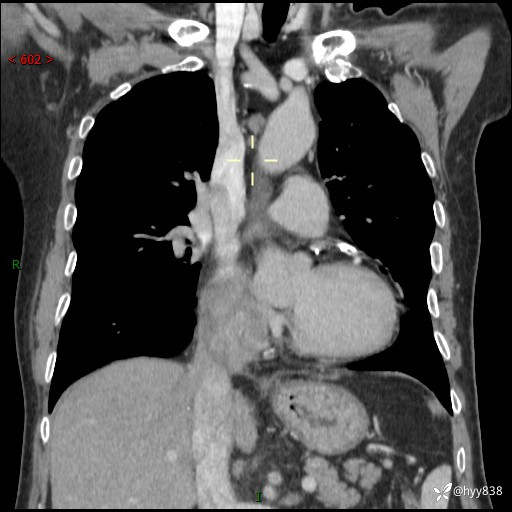

主诉:检查发现心脏肿物1周余。

现病史:患者一周余前因腹胀就诊我院消化科门诊,查心脏彩超提示右房内异常回声(粘液瘤?),无明显心慌、气喘、胸闷,无明显胸痛、咳嗽咳痰等不适,活动量增加后出现心慌、气喘不适。现为求进一步治疗,就诊我科,门诊遂以“心脏肿物”收入院。 自发病以来,精神睡眠一般,食欲尚可,大小便正常,体力下降,体重无明显变化。

胸部CT平扫+增强